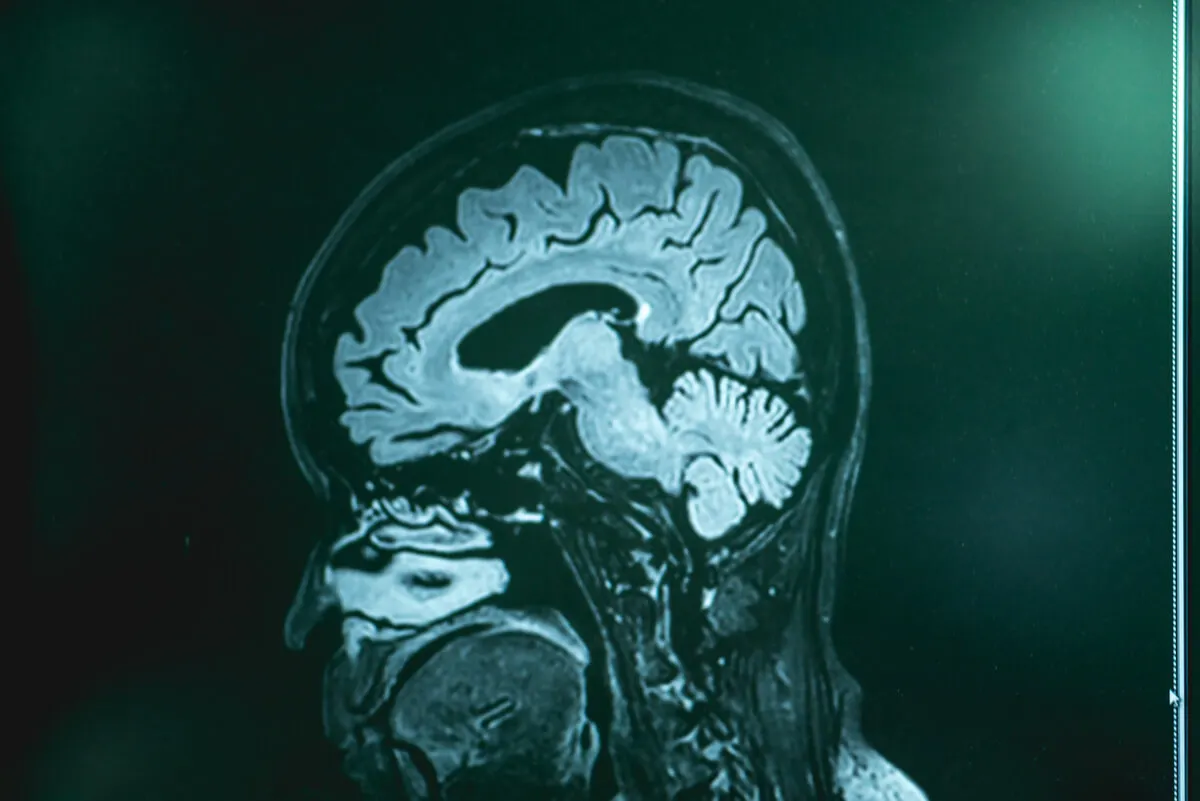

Una de las más utilizadas es la resonancia magnética. Esta imagen permite observar con detalle los tejidos cerebrales. Es probable que también se prescriban análisis de sangre y de líquido cefalorraquídeo. Para obtener este último se debe concretar una punción lumbar.